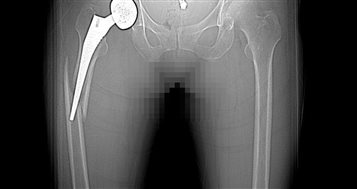

患者吴女士,在做髋关节置换术3周后不慎摔倒,当时髋部、大腿疼痛,下肢不能活动。患者家属了解到我院外二科苏纯柱主任在骨科疾病的治疗方面经验丰富,手术效果非常好。患者家属立即联系苏纯柱主任,苏纯柱主任了解到患者病情后,初步考虑患者存在两种情况:①髋关节脱位②髋关节假体周围骨折。患者来院后拍片检查证实患者假体周围骨折,患者骨折移位明显,严重影响生活质量。

苏纯柱主任介绍随着人口老龄化及人工关节的普及,假体周围骨折的数量逐年上升,由于患者多为老年人,伴有骨量减少、骨质疏松、骨质丢失严重;假体周围骨折的治疗比较复杂。本例患者髋关节置换术后3周,结合拍片考虑患者假体稳定,因此不需要处理髋关节假体,仅行假体骨折固定即可达到满意效果。